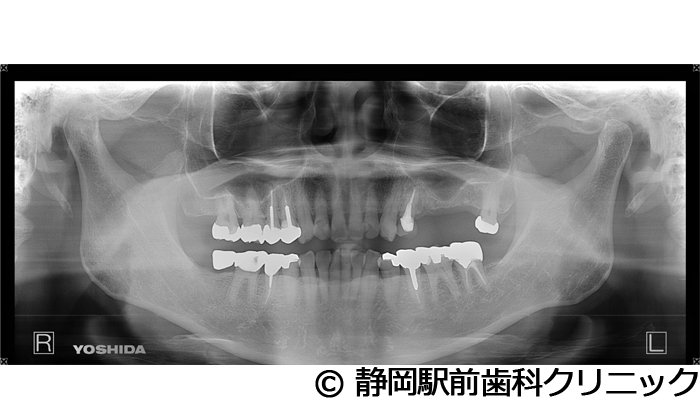

【症例3】右下インプラント埋入

- 治療前

- 治療後

- 治療名

- 右下インプラント埋入

- 費用

- 440,000円(税込)

- 期間

- 6ヵ月

治療内容

患者様の症状

右下の歯が折れてしまい、食べにくいため、インプラント治療希望。

治療方法

右下2本は抜歯を行い、骨の治癒後にCTを撮影し、詳細に治療計画を立案しました。その後、インプラントを埋入し、人工歯を被せて咬合の回復を行いました。

治療結果

患者様からは右でも好きな物を食べることができるようになり、喜んでいただきました。人工歯はセラミックにて作成し、見た目もご満足いただけました。

※治療結果は個人差があります。

治療を行う上での注意点(リスク・副作用)

術後は、出血、腫れ、痛みなどが出る可能性があります。